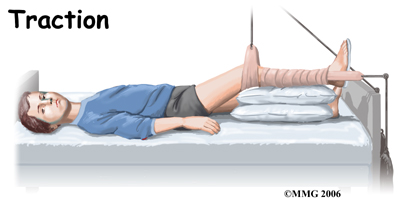

When lack of motion has become a problem, the child may be admitted to the hospital and placed in traction. Traction is used to give the joint some space and therefore quiet the inflammation. The rest for the joint while in traction also helps to settle the inflammation. Settling the inflammation usually takes about a week. Home traction may also be an option.

Chiropractic while in the hospital is used to restore the hip motion as the inflammation comes under control. A Chiropractor will visit your child in their room and assist them with some gentle hip rotation and abduction exercises (taking the leg out to the side.) These exercises will maintain and improve range of motion but will also assist in moving the fluid inside the hip joint, which assists with joint nutrition and is crucial to healing. They will also show you and your child how to continue the exercises independently once your child leaves the hospital if you will be using a home traction unit, and may prescribe further simple exercises that your child should do once they are no longer in traction. Your Chiropractor may even recommend that your child do some exercises in the pool to take advantage of the hydrostatic properties of the water to gain range of motion with less weight bearing impact.

Chiropractic while in the hospital is used to restore the hip motion as the inflammation comes under control. A Chiropractor will visit your child in their room and assist them with some gentle hip rotation and abduction exercises (taking the leg out to the side.) These exercises will maintain and improve range of motion but will also assist in moving the fluid inside the hip joint, which assists with joint nutrition and is crucial to healing. They will also show you and your child how to continue the exercises independently once your child leaves the hospital if you will be using a home traction unit, and may prescribe further simple exercises that your child should do once they are no longer in traction. Your Chiropractor may even recommend that your child do some exercises in the pool to take advantage of the hydrostatic properties of the water to gain range of motion with less weight bearing impact.

Chiropractic while in the hospital is used to restore the hip motion as the inflammation comes under control. A Chiropractor will visit your child in their room and assist them with some gentle hip rotation and abduction exercises (taking the leg out to the side.) These exercises will maintain and improve range of motion but will also assist in moving the fluid inside the hip joint, which assists with joint nutrition and is crucial to healing. They will also show you and your child how to continue the exercises independently once your child leaves the hospital if you will be using a home traction unit, and may prescribe further simple exercises that your child should do once they are no longer in traction. Your Chiropractor may even recommend that your child do some exercises in the pool to take advantage of the hydrostatic properties of the water to gain range of motion with less weight bearing impact.

Chiropractic while in the hospital is used to restore the hip motion as the inflammation comes under control. A Chiropractor will visit your child in their room and assist them with some gentle hip rotation and abduction exercises (taking the leg out to the side.) These exercises will maintain and improve range of motion but will also assist in moving the fluid inside the hip joint, which assists with joint nutrition and is crucial to healing. They will also show you and your child how to continue the exercises independently once your child leaves the hospital if you will be using a home traction unit, and may prescribe further simple exercises that your child should do once they are no longer in traction. Your Chiropractor may even recommend that your child do some exercises in the pool to take advantage of the hydrostatic properties of the water to gain range of motion with less weight bearing impact. Surgical treatment for containment may be best in older children who are not compliant with brace treatment or where the psychological effects of wearing braces may outweigh the benefits. Surgical containment does not require long-term braces or casts. Once the procedure has been performed and the bones have healed, the child can pursue normal activities as tolerated.